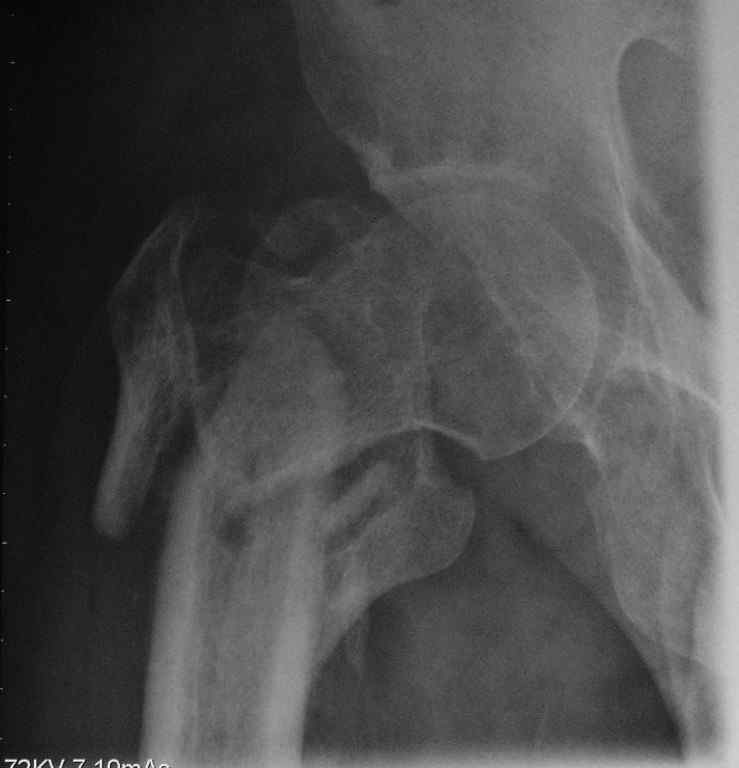

Пациент сорока лет с псевдартрозом правого бедра - исход оскольчатого чрезвертельного

перелома с отрывом большого и малого вертелов. Поступил через 8 месяцев после травмы.

По месту жительства лечили следующим образом: 2 месяца скелетное вытяжение, затем 2 месяца в

кокситной повязке. После снятия гипса дали нагрузку. В настоящий момент имеется укорочение

6 см. Патологическая подвижность. По данным КТ - сращения нет, имеется аваскулярный некроз

головки 2 стадии. В данном случае показано эндопротезирование тазобедренного сустава.